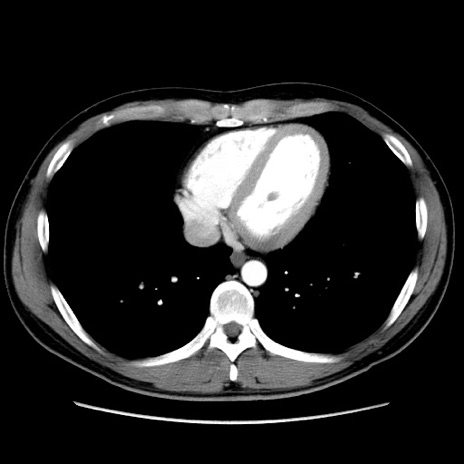

症例36(横断像)

【症例】20歳代 男性

【主訴】心窩部痛

【現病歴】今朝より上腹部痛あり。一旦軽快していたが再度出現したため救急要請。昨日夕に白身の魚を含む刺身を食べた。

【身体所見】BP 136/89mmHg、HR 74/min、BT 37.0℃、腹部:膨満、軟、心窩部に圧痛あり。反跳痛なし、筋性防御なし、腸雑音やや亢進あり。

【データ】WBC 17700、CRP 0.48